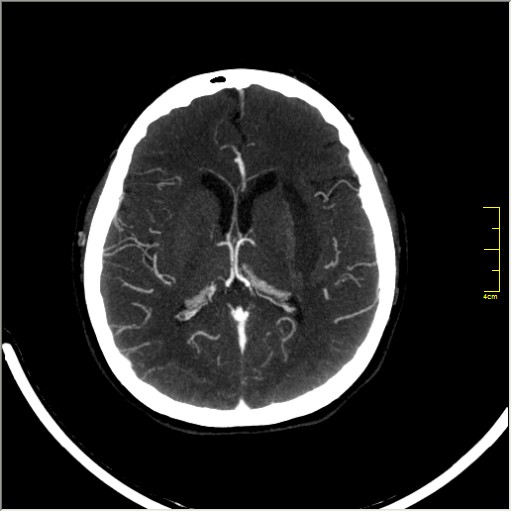

КТ ангиография головного мозга

Стандартная процедура в современной работе КТ кабинета, весьма несложна в исполнении.

Сканы представленны в режиме MIP.

Angio0.JPG

Angio1.JPG

Angio2.JPG

Angio3.JPG

Angio4.JPG